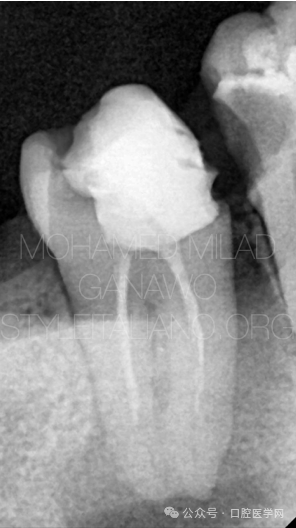

图2

彻底去除原有充填物并完成根管清理后,根管充填试尖的影像学表现如图所示。